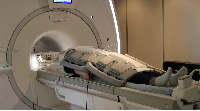

Магнитно-резонансная томография (МРТ):один из самых эффективных методов диагностики заболеваний